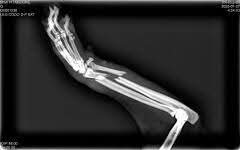

@Solopar53137293 Todavía no tenemos el presupuesto pero sí he puesto las facturas que ya se han generado y de la cual queda más de la mitad por pagar

@Beaguti33 Rt pobrissona. Poseu el pressupost de l'amputació us ajudarà a agafar diners